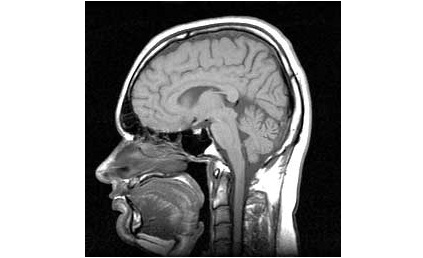

Die medizinische Forschung ist immer auf der Suche nach günstigen und zuverlässigen Diagnosemethoden für Hirnschäden. So hatten wir vor einigen Tagen von einem Forscherteam berichtet, dass die Augenbewegungen der Patienten analysiert und daraus entsprechende Rückschlüsse zieht. Eine japanische Studie hat nun eine noch simplere Methodik wissenschaftlich untersucht: Probanden wurden gebeten möglichst lange auf einem Bein zu stehen. Patienten, die dabei in weniger als zwanzig Sekunden die Balance verloren, wiesen oftmals bereits kleine Schädigungen der Hirngefäße auf. Foto: Gedächtnisleistung Ranveig mri. jpgCC BY-SA 3.0 (VIA WIKIMEDIA COMMONS) Weitere Symptome nicht erkennbar Diese kleinen Schädigungen wiederum gelten als Frühindikator für schwere Schädigungen, beispielsweise Schlaganfälle oder Demenz. Das interessante dabei: Zum Zeitpunkt des Tests wiesen die untersuchten Probanden keinerlei weiteren auffälligen Symptome auf. Der simple Bein-Steh-Test kann also helfen gefährdete Personen auf einfache Weise zu erkennen und dann genauer zu untersuchen. Unabhängig davon konnte eine kurze Balancezeit ebenfalls mit schlechten Ergebnissen bei Gedächtnis- und Logiktests in Korrelation gebracht werden. Eine Beeinträchtigung des Gehirns scheint also vorzuliegen. Test dient vor allem der Identifizierung von gefährdeten Patienten Dabei muss allerdings bedacht werden, dass es sich um kein hundertprozentig sicheres Prognoseverfahren handelt. Personen mit Gleichgewichtsschwierigkeiten haben zwar signifikant öfter kleine Gefäßschädigungen als Dauerbalancierer. Aber nicht jeder, der frühzeitig den zweiten Fuß zu Hilfe nehmen muss, hat auch zwingend einen Hirnschaden. Um einen solchen mit absoluter Sicherheit feststellen zu können, müssen andere Testmethoden zum Einsatz kommen. Bereits vor einiger Zeit haben Tests allerdings belegt, dass die Fähigkeit auf einem Bein zu balancieren, Auskunft über die Wahrscheinlichkeit eines frühzeitigen Ablebens geben kann. Wie das „Medical Research Council“ herausfand, sind 53-jährige Männer, die länger als zehn Sekunden auf einem Bein stehen können und in der Lage sind sich in einer Minute mindestens 37 mal von einem Stuhl zu erheben deutlich seltener von einem frühen Tod betroffen, als Leute, die an dieser Aufgabe scheitern. Quelle: Digital Journal Teile den Artikel oder unterstütze uns mit einer Spende. Facebook Facebook Twitter Twitter WhatsApp WhatsApp Email E-Mail Newsletter